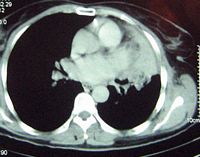

On admission, the patient had a 38°C temperature, 87 beats/min pulse, 130/70 mmHg blood pressure with a 95% oxygen saturation while breathing room air. Respiratory crackles were heard over the left lung field. The rest of the clinical examination was normal. Full blood count, serum chemistries, renal and liver function tests were normal. The screening for human immunodeficiency virus was negative. Sputum cultures were sterile for bacteria, fungi and acid fast bacilli. A bone marrow aspirate and biopsy was normal. A chest X- Ray revealed a left parahilar opacity (Figure 1). Chest CT-scan (Figure 2) revealed a bronchial tumour mass of the left superior lobe classified as T3N0MO: stage IIIA. Bronchoscopy showed an incomplete stenosis by an infiltration of the upper lobe. Biopsies revealed nonspecific inflammation. An extrapericardic left pneumonectomy was performed because of the high suspicion of lung carcinoma. The immuno-histochemical staining showed a polymorphous lymphoid infiltrate expressing CD3+ T cells and CD20+ and CD30+ B cells, and a perivascular infiltrate with extensive tissue necrosis in keeping with angiitis; these findings were consistent with the diagnosis of LYG grade 2 by WHO classification (Figure 3). The patient refused any adjuvant chemotherapy. There was no evidence of any clinical or radiological signs of relapse three years after surgery (Figure 4).

Figure 2. Chest CT-scan showing a bronchial tumour mass of the left superior lobe.